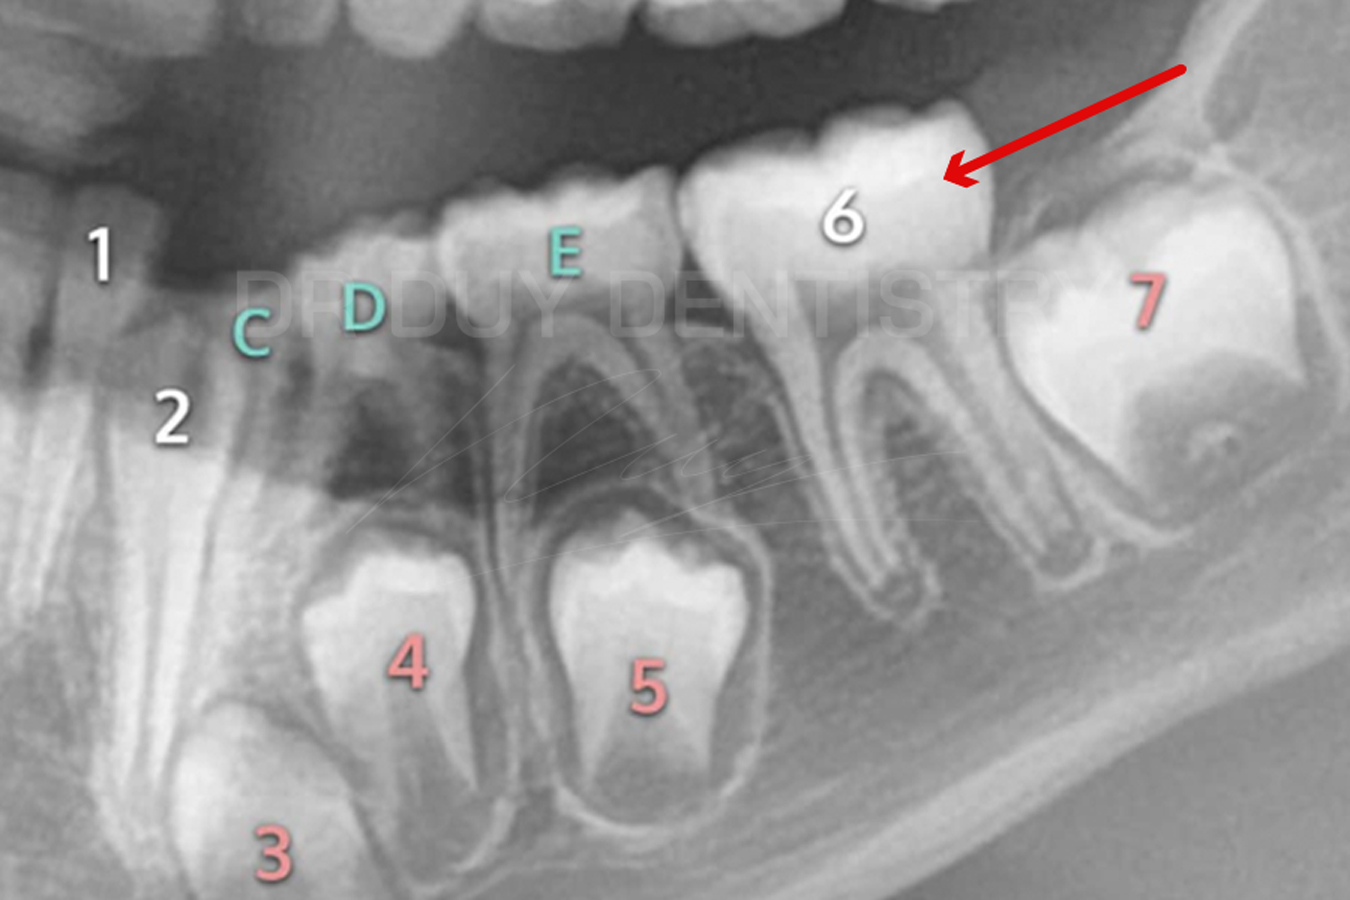

- Răng số 6 hay còn gọi là răng 6 tuổi, đây là chiếc răng cối lớn vĩnh viễn đầu tiên mọc lên khi trẻ 5-6 tuổi.

- Răng số 6 mọc lên ở vị trí phía sau răng cối sữa thứ 2 và không thay thế cho các răng sữa trước đó.

- Hay nói cách khác, chiếc răng này mọc thêm bên cạnh các răng sữa hiện tại của trẻ, do đó rất nhiều phụ huynh nghĩ rằng đây vẫn là răng sữa vì chưa thấy trẻ thay răng.

Răng số 6 hàm dưới trong cùng